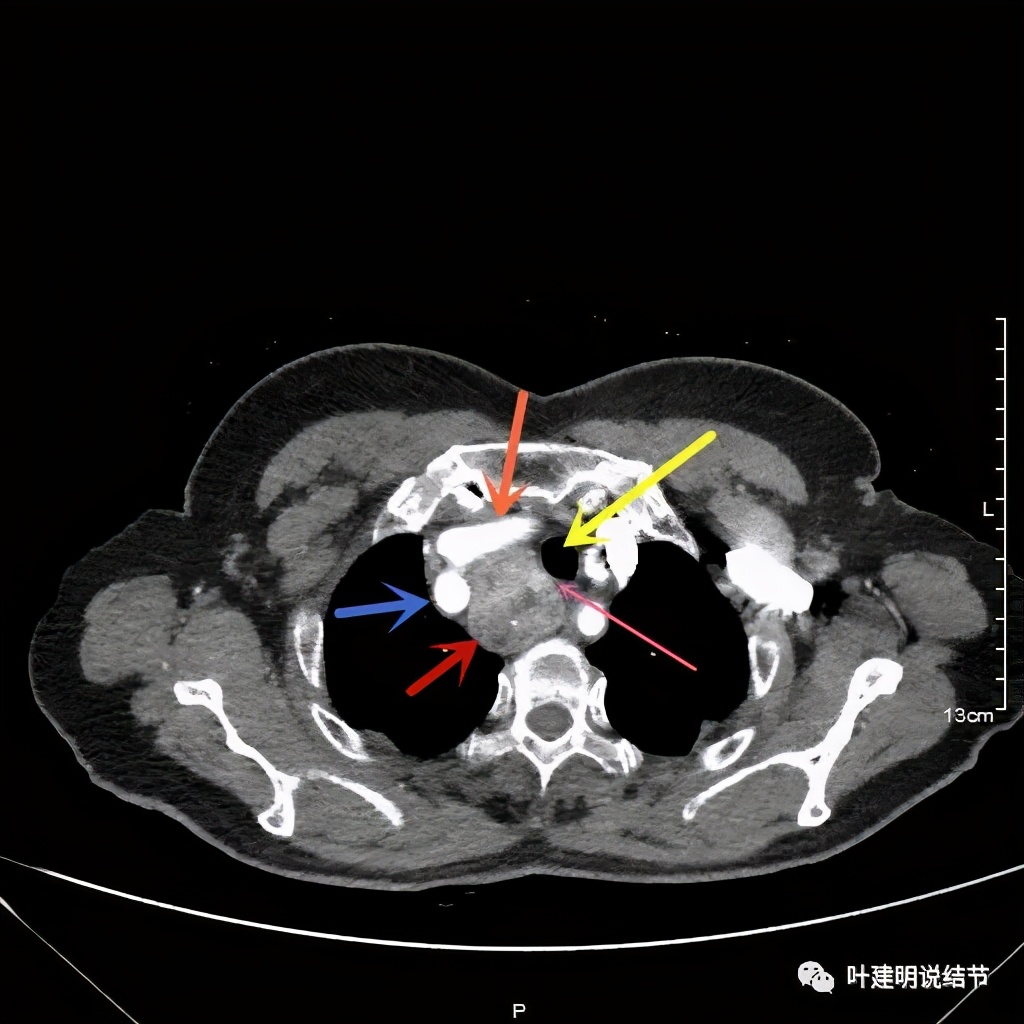

上图红色示肿瘤,黄色示气管,粉色示肿瘤与气管关系密切,桔色示左无名静脉,蓝色示上腔静脉,而且肿瘤密度不均杂乱

上图红色示肿瘤,黄色示气管,桔色示左无名静脉,蓝色示上腔静脉,而且肿瘤密度不均杂乱